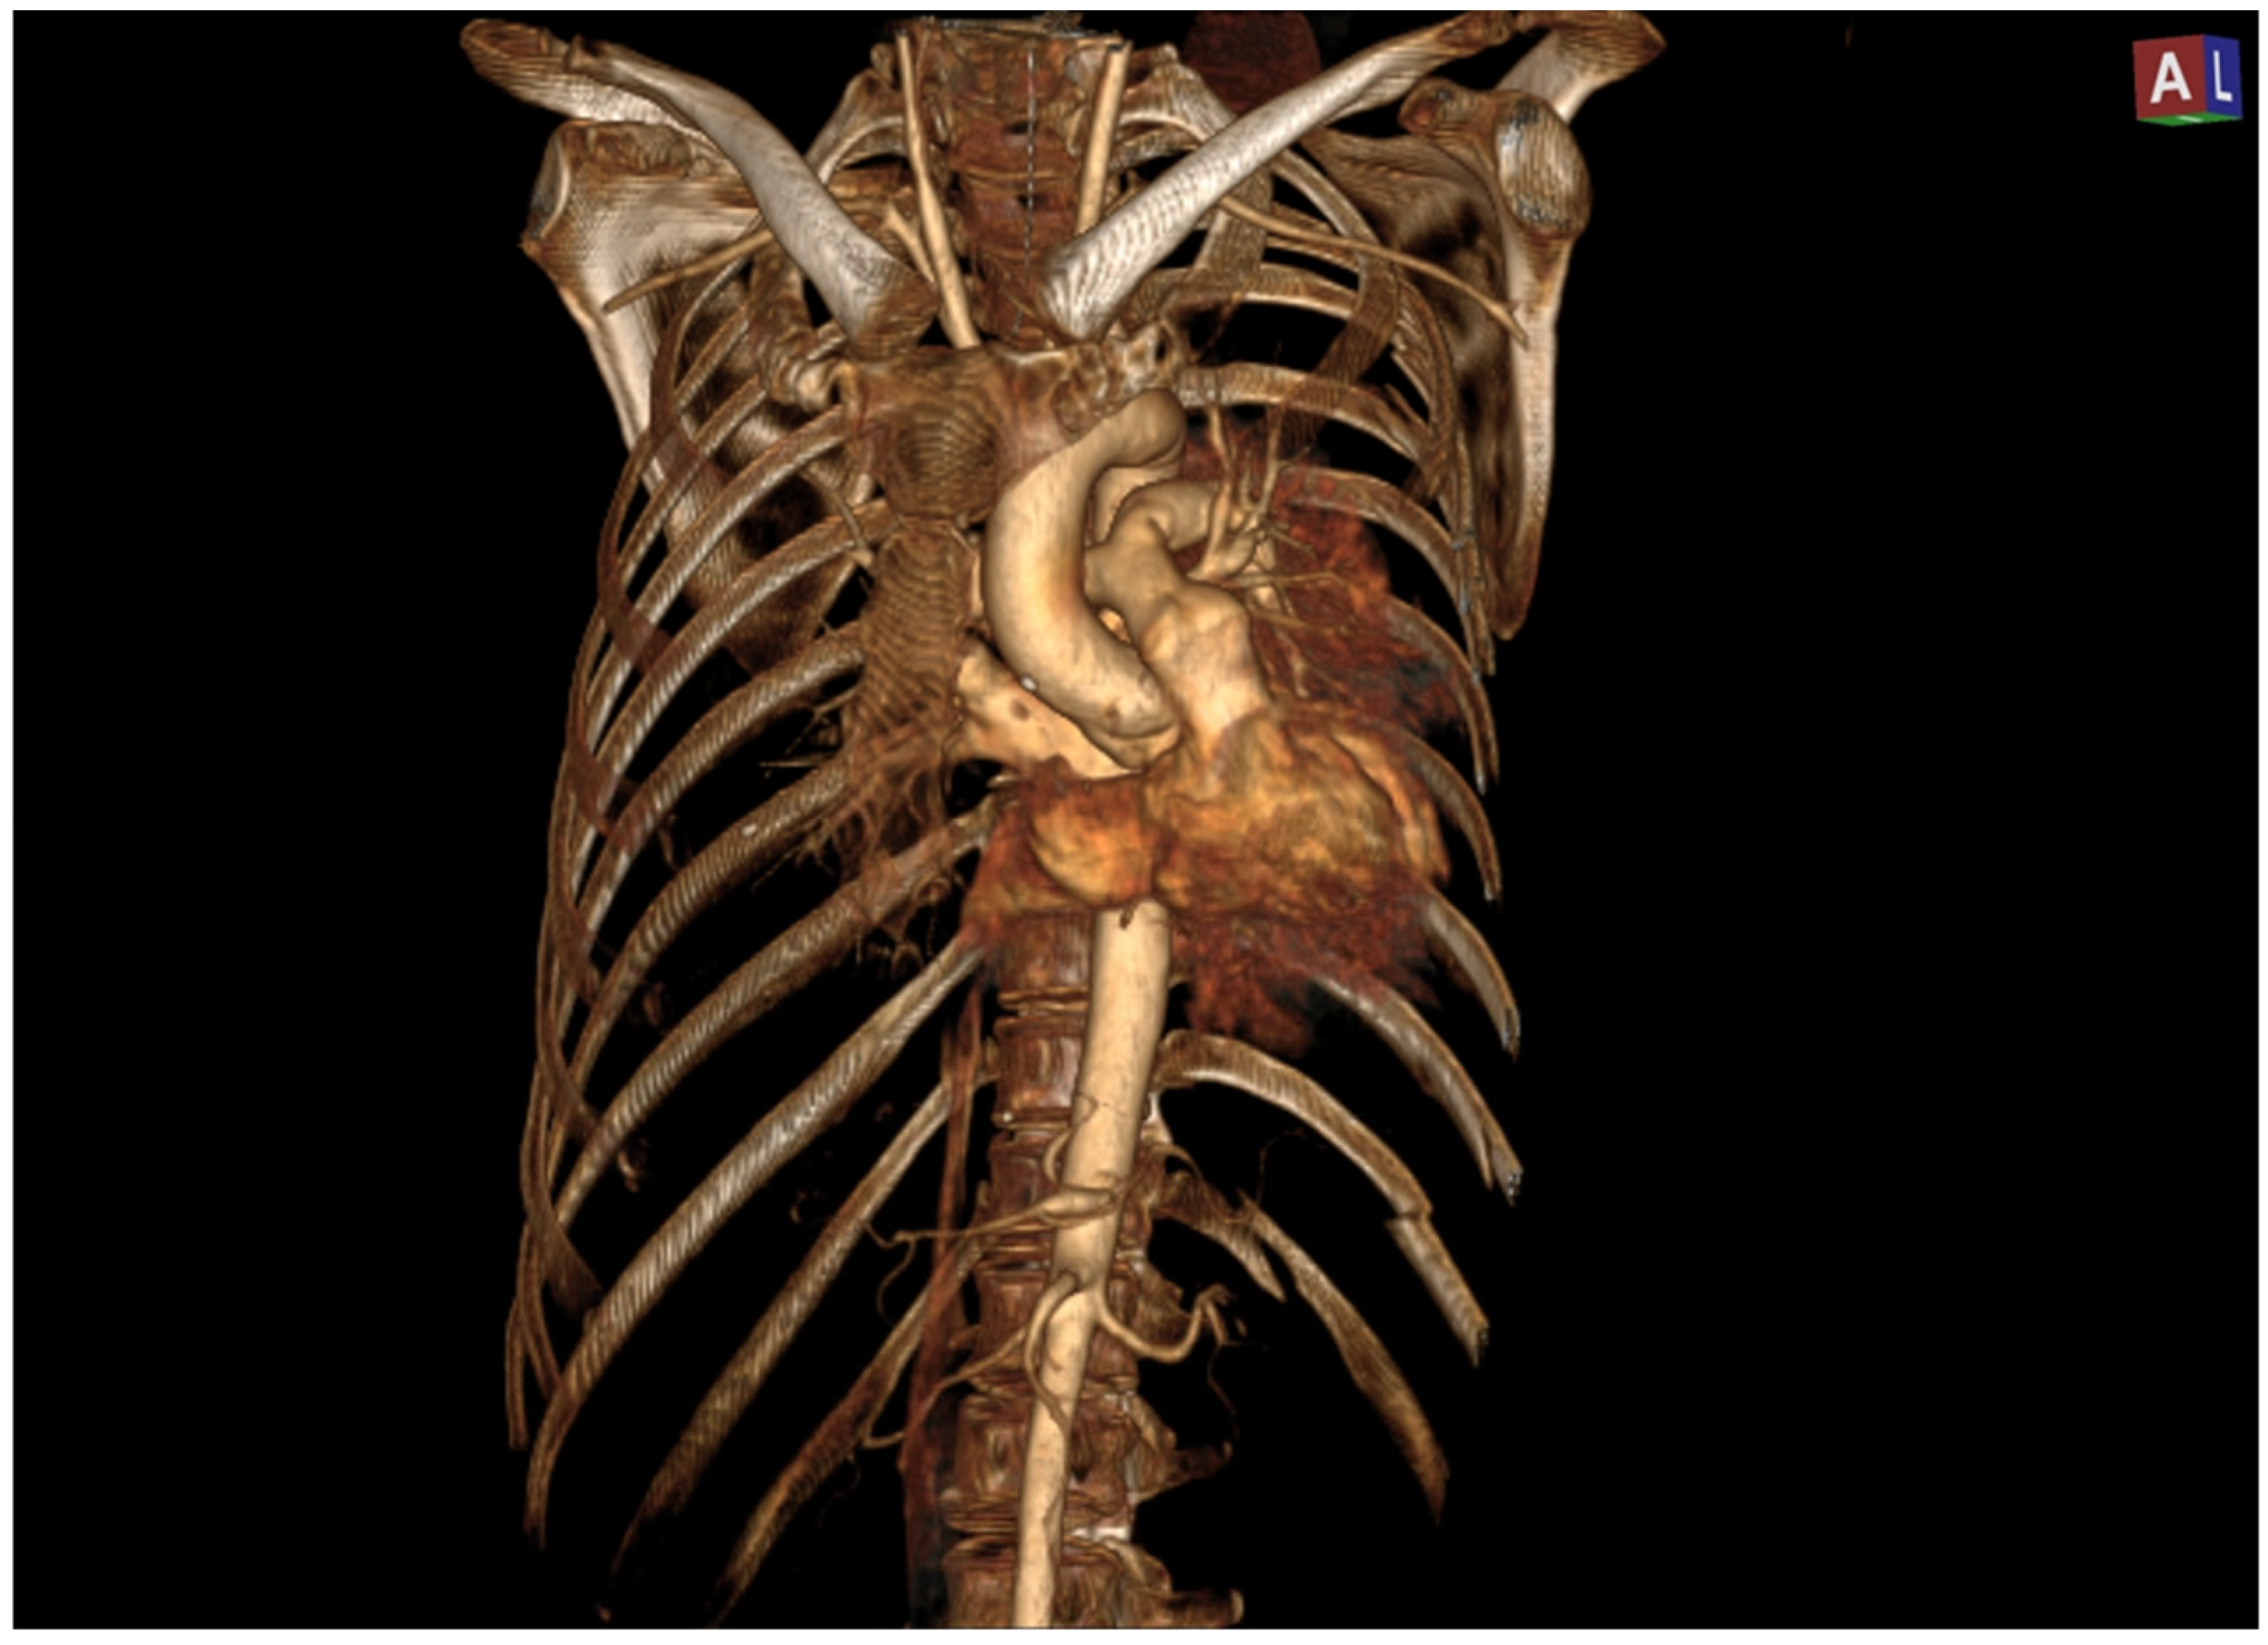

After an expeditious evaluation at the trauma center, a computed tomography (CT) scan revealed that the heart was completely dislocated within the left lung, attributable to a traumatic rupture of the pericardium (Figure 1). Other additional findings included a substantial pneumomediastinum associated with a moderate left pneumothorax, foci of consolidation in the lower lobe, “ground-glass opacities” involving the middle lobe suggestive of parenchymal contusion, no traumatic rupture of the major blood vessels, and no cardiac tamponade.

Figure 1. Computed axial tomography showing heart dislocation. P: posterior side.